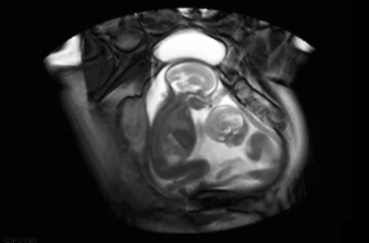

很多人都講究好事成雙,在生孩子方面也有不少女性希望自己能生雙胞胎,那么吃排卵藥真的能生雙胞胎嗎 哪種人適合吃排卵藥備孕.下面八寶網的小編就來介紹。

促排卵藥是處方藥,原是為一些無法自然排卵的女性患者而研制,所有的藥物都是醫生根據患者情況開處方后服用的,不能自己隨意服用; 在沒有醫生監護的情況下服用是非常危險的,可能會打亂女性排卵規律;造成卵巢過度刺激綜合癥;增加胎兒發育畸形的幾率。服用排卵藥之后是單胎、雙胎還是多胎也不是自己能控制的事情。絕對不能服用來源不明的非法藥物。